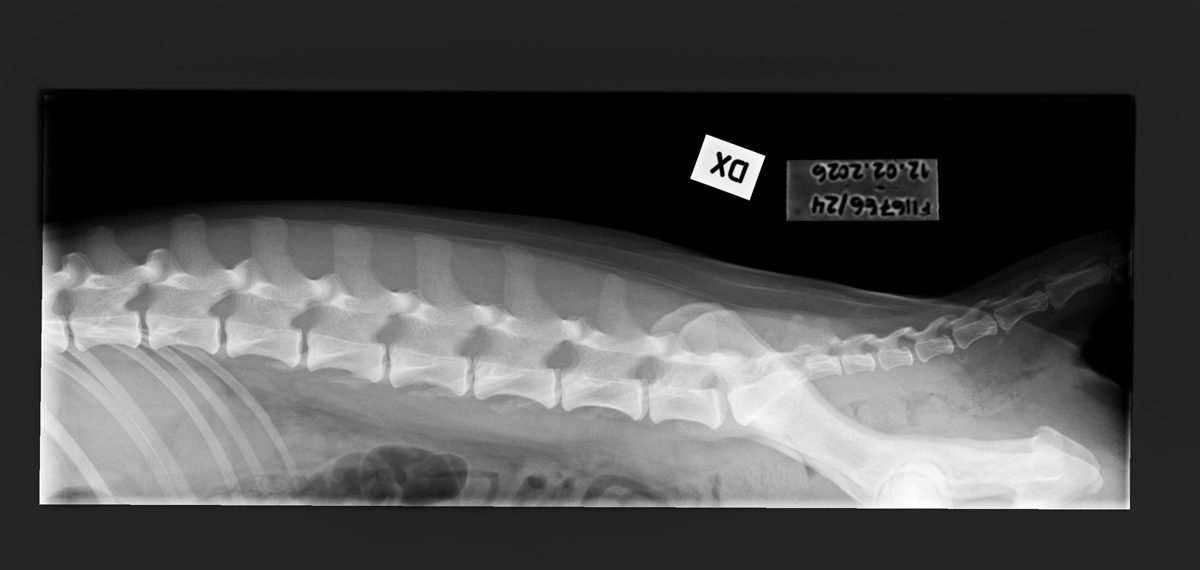

- Free of lumbosacral transitional vertebrae (LTV0)

- Free of spondylosis (SP0)

- Free of vertebral anomalies (VA0)

- Spine x-rays: 1, 2 ja 3

- Spine x-rays: 1, 2, 3